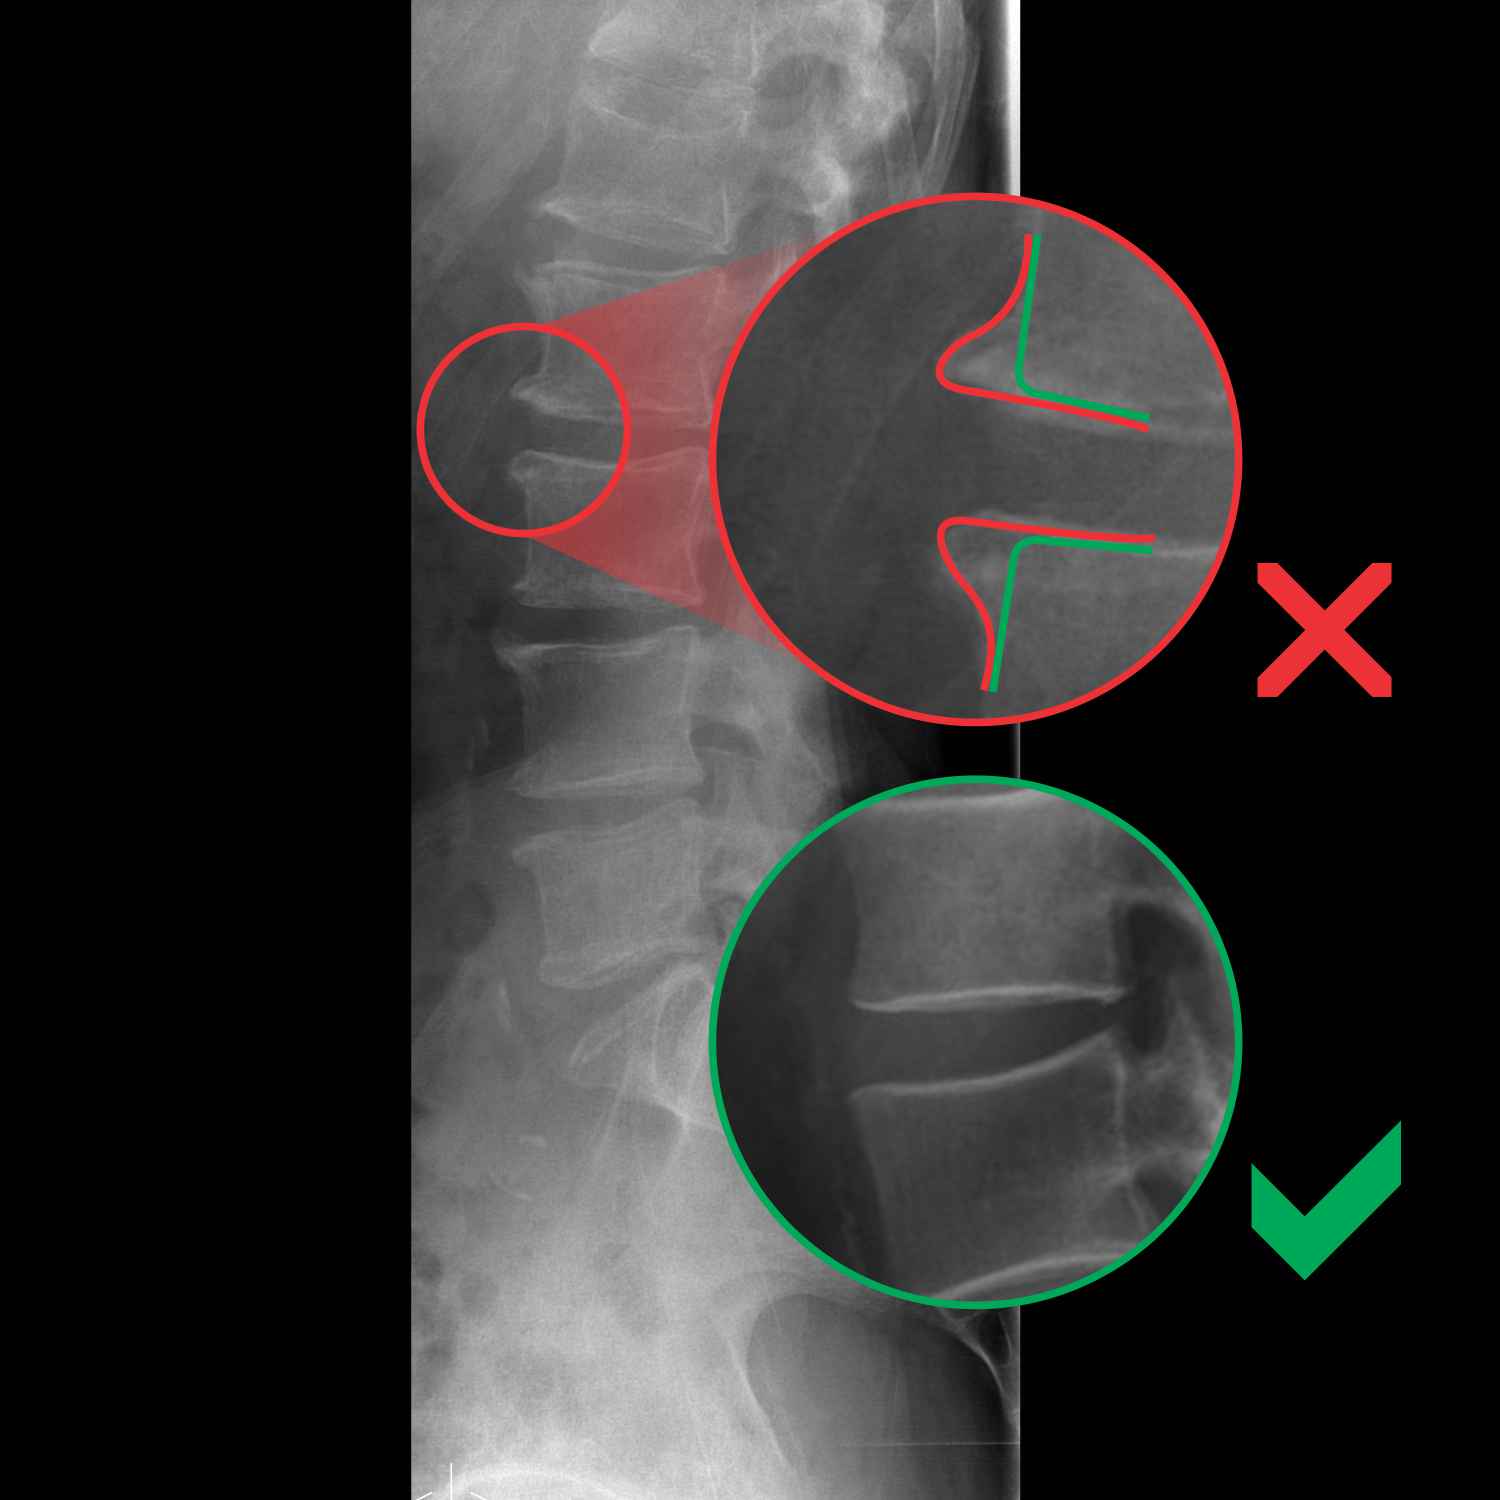

MRI spondiloza, izrastki iz vretenc, hrbtenica

Slika magnetne resonance (MRI) - spondiloza

Vretenca niso pravilnih oblik. Na njih so vidni izrastki, ki štrlijo navzven.